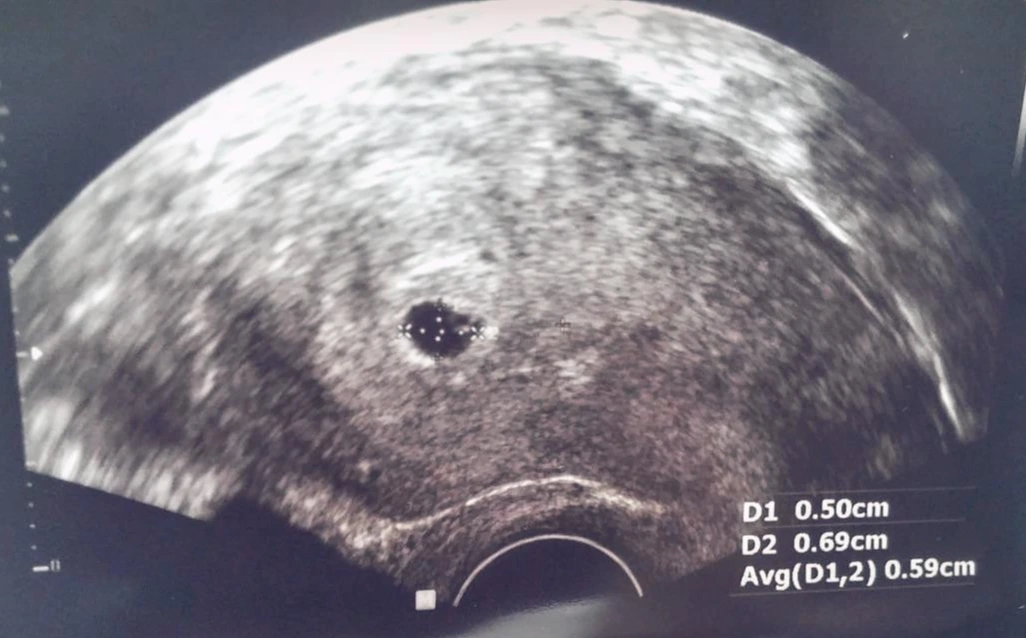

'16년도에 업무 때문에 구정을 끼고서 장기간 러시아 크림반도로 출장길에 올랐던 것을 시작으로 공장 파견에 상당히 많은 일정이 겹치던 시기였다. 귀국 후 한 2~3주 지나서 공장에 파견 나가 있는 동안 아내로부터 받은

사진 하나...

아직은 정확히 감도 안 오고 어떠한 느낌인지도 알 수 없으나 굉장히 복합적인 감정이 순간 올라왔던 기억이 있다. 환희, 설렘, 의아함, 두려움, 걱정, 다급함 등 다양한 감정들이 온종일 머릿속을 왔다 갔다 한다. 기쁨이 제일 클 것이라고 생각하겠지만 얼떨떨 한 부분이 제일 컸던 것 같다.